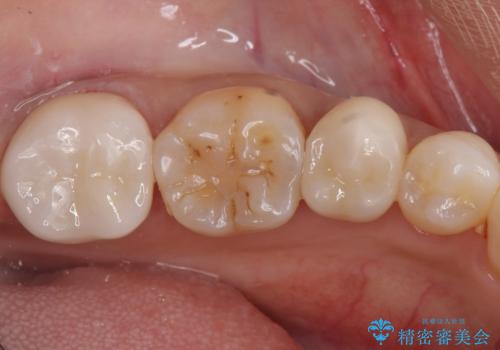

- 左下7 仮歯+e-maxクラウン:11,000円+77,000円費用は治療当時の料金となります

今回の場合、虫歯の大きさが大きく本来であれば歯茎に対しても治療をすることが検討されケースですが、ご希望されなかったため被せ物のみでの治療となりました。